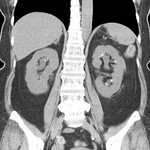

[画像診断]腎盂腎炎とCTについて【初期研修医と学ぶ】 2010-08-25